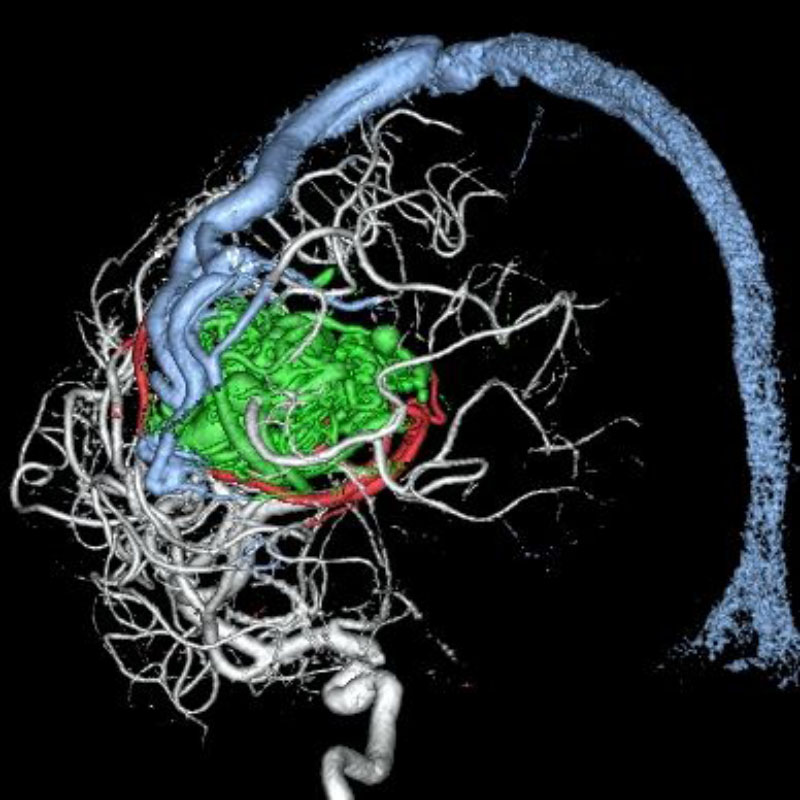

脳動静脈奇形

血管塞栓術

松田/濵田/元永